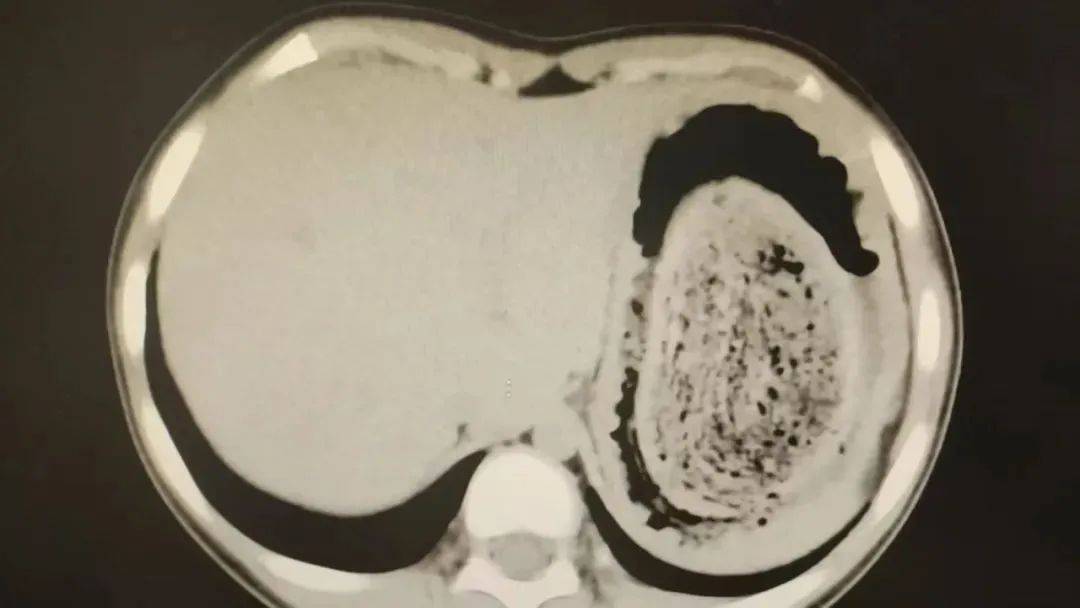

结果出来时,医生都惊呆了:小可的胃里,塞满了成团的头发,几乎占了胃容量的四分之三皇冠登3代理出租。大量不能消化的物质,在胃酸的作用下发生变性,并与食物及其他物质结合形成团块,慢慢变成坚硬的“胃石”。

2024年10月,11岁女孩欢欢(化名)因腹痛难耐紧急送到医院,而就在两个月前,欢欢的父母发现她在拔自己的头发,偷偷吃掉皇冠登3代理出租。经检查,医生发现她胃腔和肠管里有大块的毛絮状结石,几乎占据整个胃部。最终,一块长38厘米、宽15厘米、厚10厘米的毛发结石被取出。